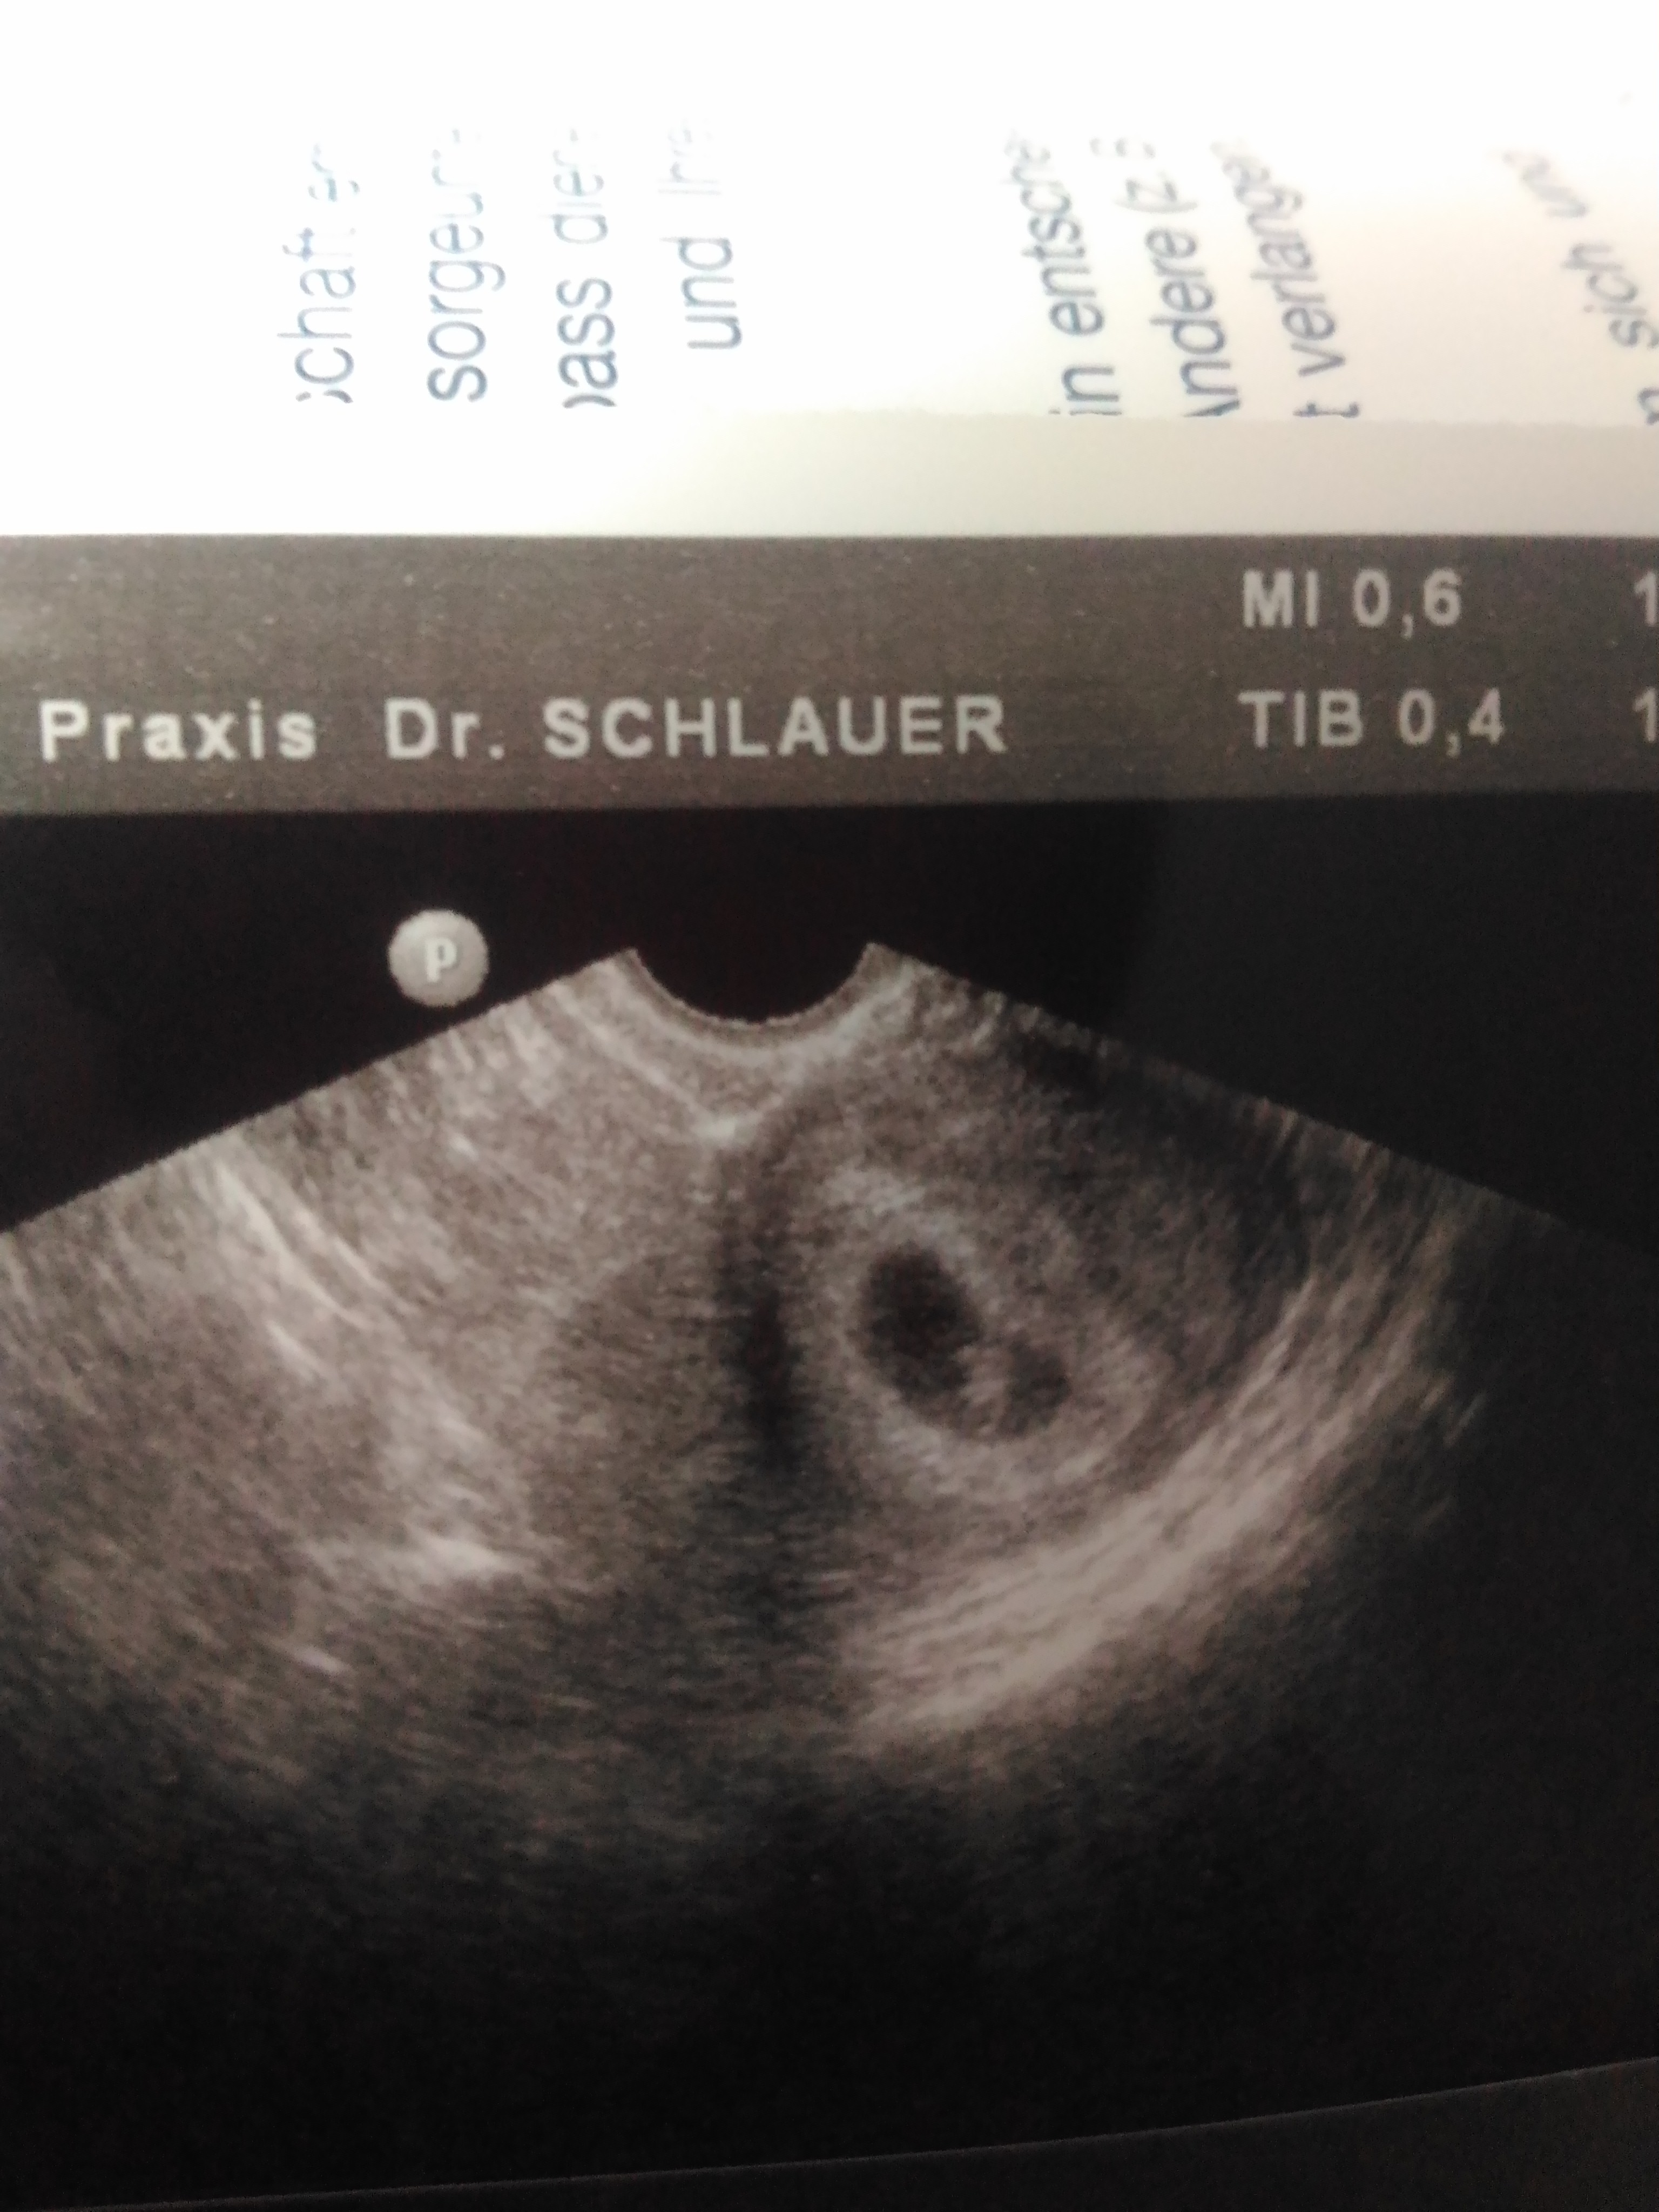

U mnie też wszystko dobrze :) 9mm szczęścia i serduszko też sobie pikało ;)

• P_20190118_121009.jpg

P_20190118_121009.jpg

1,3 MB · Wyświetleń: 115

Tak patrze na twoje usg i zastanawiam się czy miałaś brzuszne czy dopochwowe?

Bo ja swoje usg ze szpitala miałam robione brzuszne, u ciebie wszystko pięknie wiadac a u mnie to ja nic nie widzę ;(

Miałam dopochwowe.